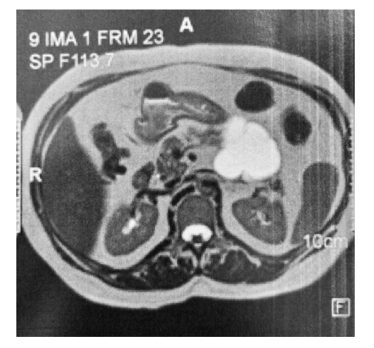

Um homem de 52 anos de idade apresenta a lesão pancreática assintomática mostrada a seguir.

Com base nesse caso hipotético, é correto afirmar que a lesão menos provável com relação ao diagnóstico final é o(a)